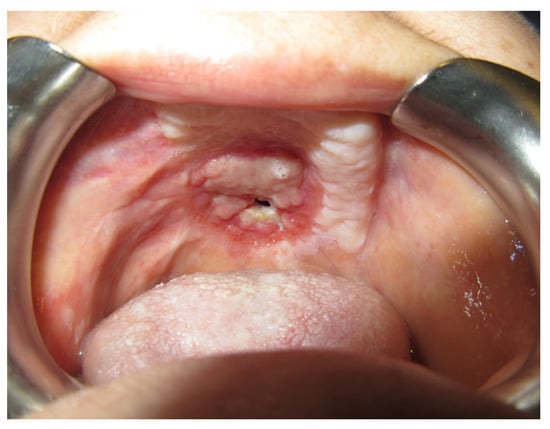

3.1.1. Case 1: A.R.